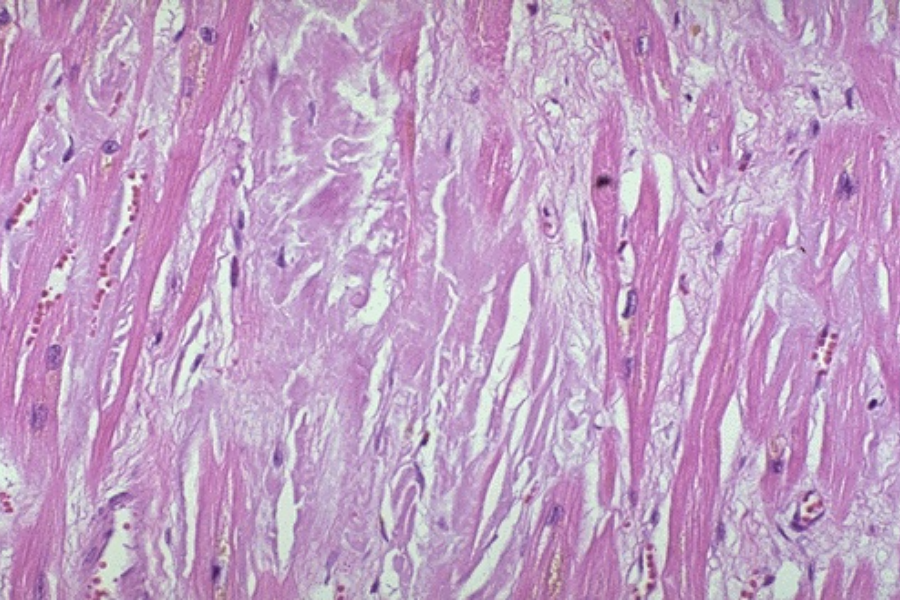

histologische Bilder

adultes Myokard adultes Myokard

hypertensive Herzkrankheit hypertensive Herzkrankheit

hypertrophe Kardiomyopathie hypertrophe Kardiomyopathie

kardiale Amyloidose kardiale Amyloidose

kardiale Hämochromatose kardiale Hämochromatose

Glykogen-Speicherkrankheit Glykogen-Speicherkrankheit

Pathology Residency and Fellowship Program, Brown University, Access 23. October 2022

Elliott P, McKenna WJ (2004) Lancet 363:1881-1891

Internet Pathology Laboratory , University of Utah, Access 23. October 2022

Thoracic Pathology, Cardiac Hemochromatosis, Access 23.October 2022